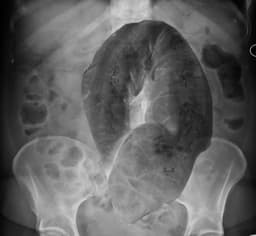

- Sigmoid volvulus occurs when the sigmoid colon twists 180 to 360 degrees

- 10% of intestinal obstructions in the US; 50-70% of intestinal obstructions worldwide

- More common in elderly patients with chronic constipation

- Eventually may lead to bowel perforation, a surgical emergency

- Treatment is sigmoidoscopy or sigmoid colectomy